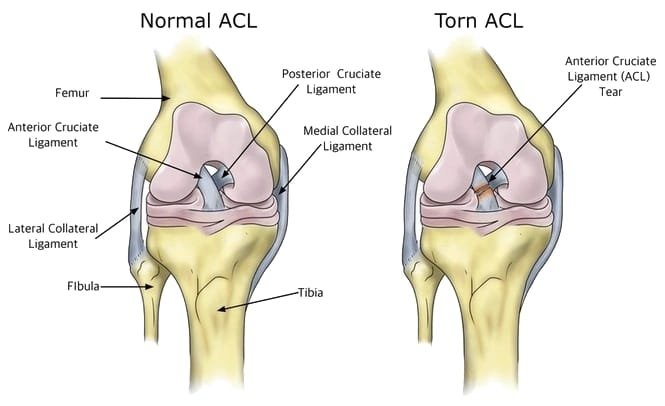

ACL reconstruction restores knee stability after ligament injury, commonly caused by sports or sudden twisting movements. The torn ligament is replaced with a graft to support confident movement and prevent further damage. With structured rehabilitation and strengthening, patients can safely return to sports and active lifestyles. The procedure also helps reduce the risk of future knee instability and joint degeneration.

ACL surgery is performed to restore stability to the knee after a ligament tear, which often occurs during sports or sudden twisting movements. The damaged ligament is reconstructed using a graft, providing strength and stability needed for high-impact activities. Minimally invasive arthroscopic techniques allow for smaller incisions and faster recovery.

The choice of graft—whether from the patient’s own tissue or a donor—depends on lifestyle, activity level, and overall health. Modern surgical methods ensure precise placement of the graft, replicating the natural anatomy of the ACL. This significantly reduces the risk of reinjury and enhances long-term knee stability.